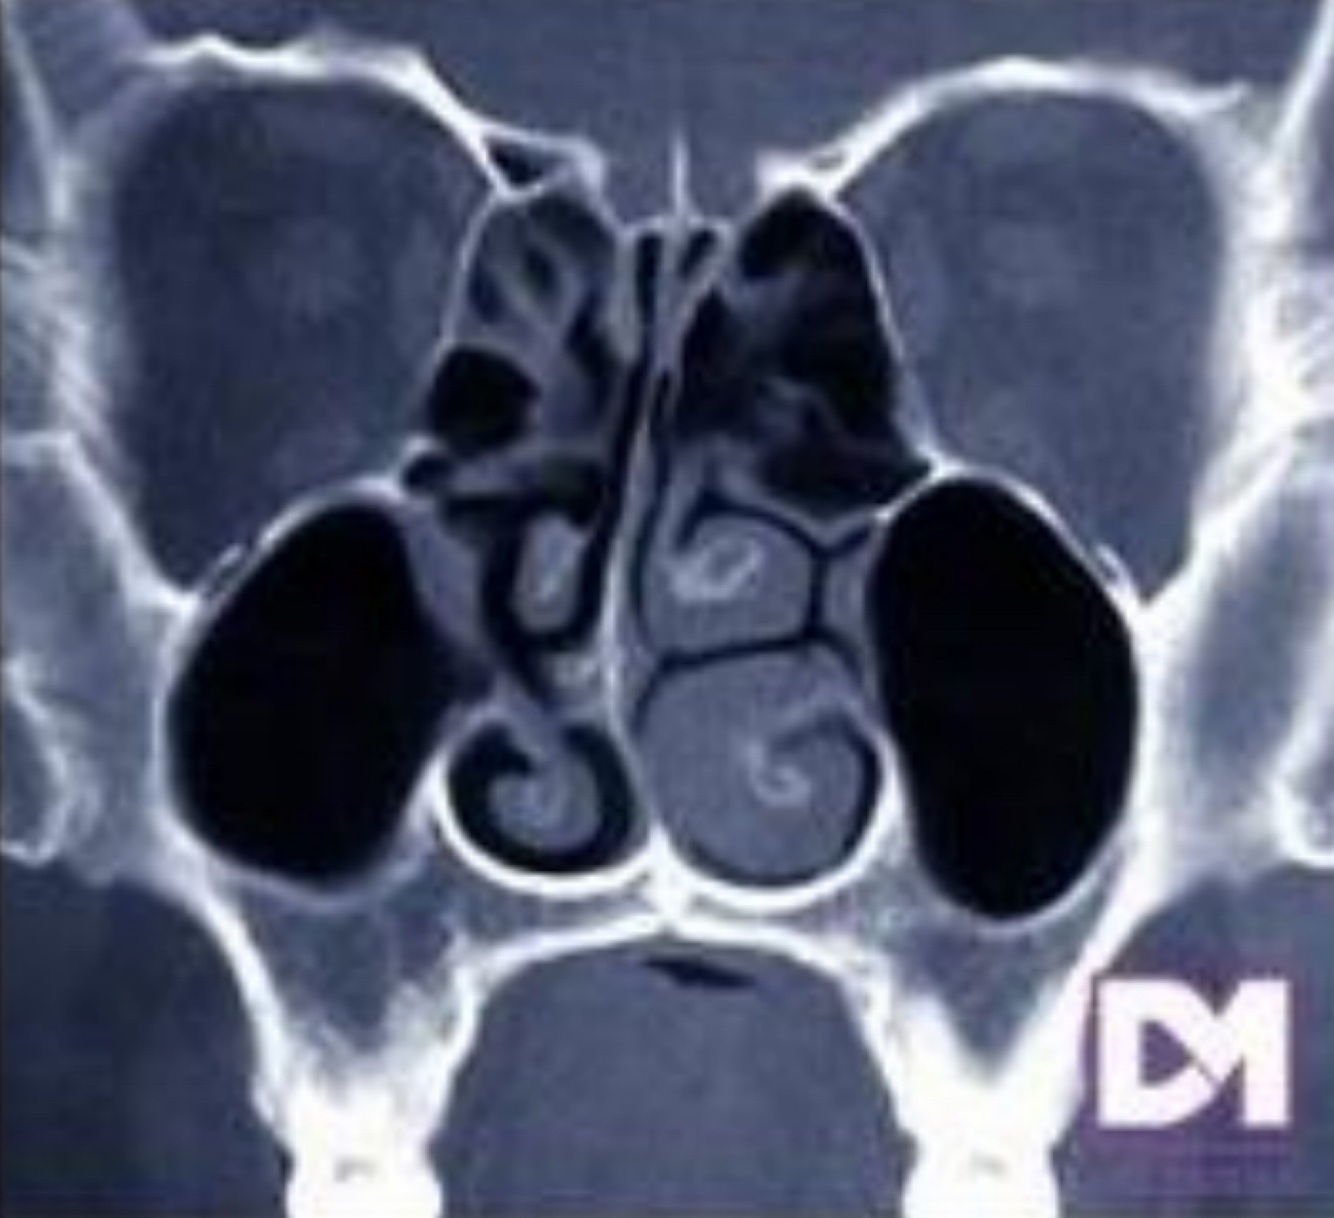

Q

Cornete medio paradójico